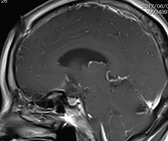

錐体斜台部髄膜腫

この部位は脳神経がすだれのように走行しており、腫瘍により脳幹・脳神経(外転神経・顔面神経・聴神経など)が圧迫されると物が2つに見えたり、耳が聞こえなくなったり、さらに腫瘍のサイズが大きくなると生命に危険な状態となります。

(術後MRI)

このように比較的大きい腫瘍が脳幹を圧迫している場合は、重篤な症状をきたし生命に危険が伴う可能性があるため、早急に手術が必要です。